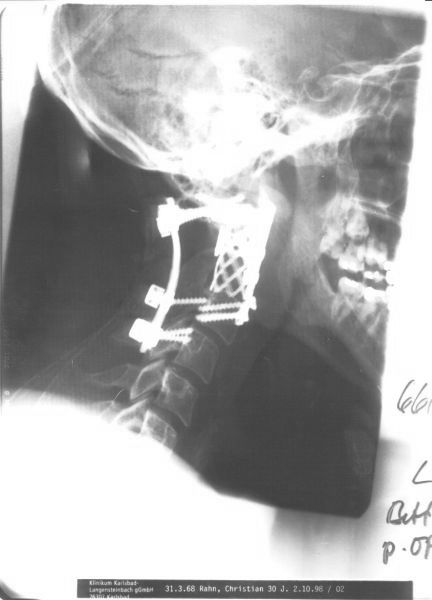

Mein Hals nach der OP (Entfernung des 2. Halswirbels)